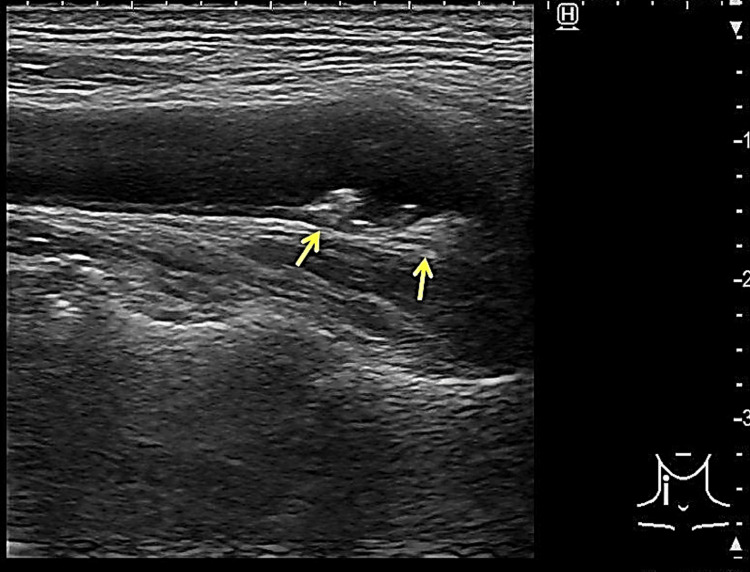

Figure 2. The result of carotid ultrasound.

Carotid ultrasound showing plaques of the bilateral carotid bulbs (arrowheads, this echogram is the right side).

| First dorsal interosseous muscle | 3 | Ulnar nerve | C8, T1 |

Blood tests were unremarkable except for slightly elevated C-reactive protein (0.32 mg/dL), blood glucose (118 mg/dL), and γ-glutamyl transpeptidase (75 U/L). Nerve conduction studies revealed normal results. Diffusion-weighted and T2-weighted fluid-attenuated inversion recovery brain MRI showed hyperintensity in PK on the left precentral gyrus (Figure 1). Brain magnetic resonance angiography showed no occlusion of the major artery. Transesophageal echocardiography showed no thrombus, right-to-left shunt, or aortic arch lesion. Carotid artery echocardiography revealed plaques on both bulbuses and thickening of the intima media thickness (IMT), but no increment of blood flow velocity (Figure 2).